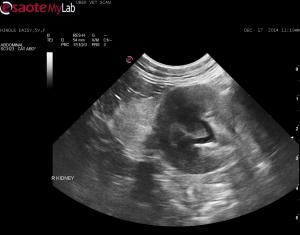

– both kidneys mildly enlarged, surrounded by ill-defined, bright hyperechoic fat and mild pylectasia

– a trace amount of subcapsular fluid noted around the right kidney at the caudal pole (second clip shows this)